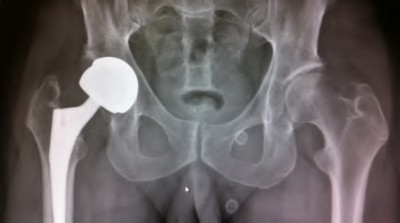

A 45-year-old female with developmental dysplasia of the hip (DDH) presents for THA. Preoperative radiographs show the femoral head is subluxated, with 80% proximal migration relative to the height of the normal true acetabulum. Based on the Crowe classification, what type of dysplasia does she have?